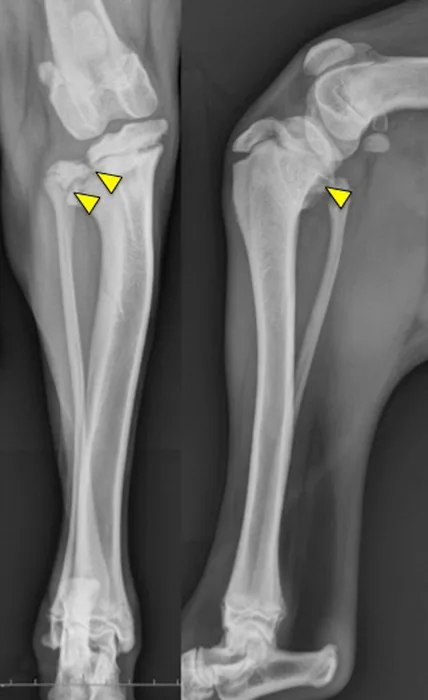

Physeal fractures can occur in any juvenile animal, even with little trauma, because the physis is weaker than the adjacent bone and ligaments. Orthogonal radiographs of any painful joint should be performed. Oblique projections, radiographs of the limb in different positions, and radiographs of the contralateral limb for comparison can all aid in the diagnosis of a physeal fracture. Shown here are lateral stifle radiographs from an 8-month-old mixed breed dog that presented for acute onset of lameness in the left pelvic limb after he slipped earlier that evening; pain was localized to the left stifle. Notice the open physes of the proximal tibia and distal femur, which are normal for a dog of this age. There is physeal separation and cranial displacement of the proximal epiphysis in the left tibia, and a greenstick fracture of the left fibula (arrows).